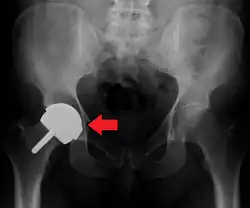

Dislocated artificial hip

Liner wear, particularly when over 2 mm, increases the risk of dislocation.[15] Liner creep, on the other hand, is normal remoulding.[16]

Dislocation (the ball coming out of the socket) is one of the most common complications. Hip prosthesis dislocation mostly occurs in the first three months after insertion, mainly because of incomplete scar formation and relaxed soft tissues.[15] The chance of this is diminished if less tissue is cut, if the cut tissue is repaired and if large diameter head balls are used.[17] Surgeons who perform more operations tend to have fewer dislocations. Important factors which are related to dislocation are: component positioning, preservation of the gluteal muscles and restoration of leg length and femoral offset.[18] Keeping the leg out of certain positions during the first few months after surgery further reduces risk.